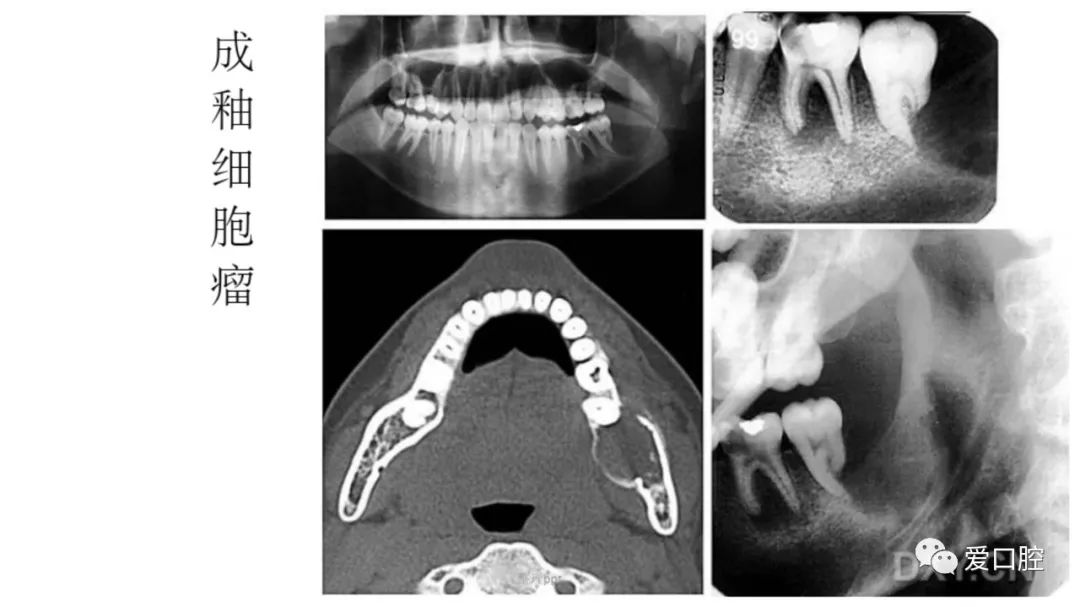

口腔小技巧 | 口腔科常见的病例影像!